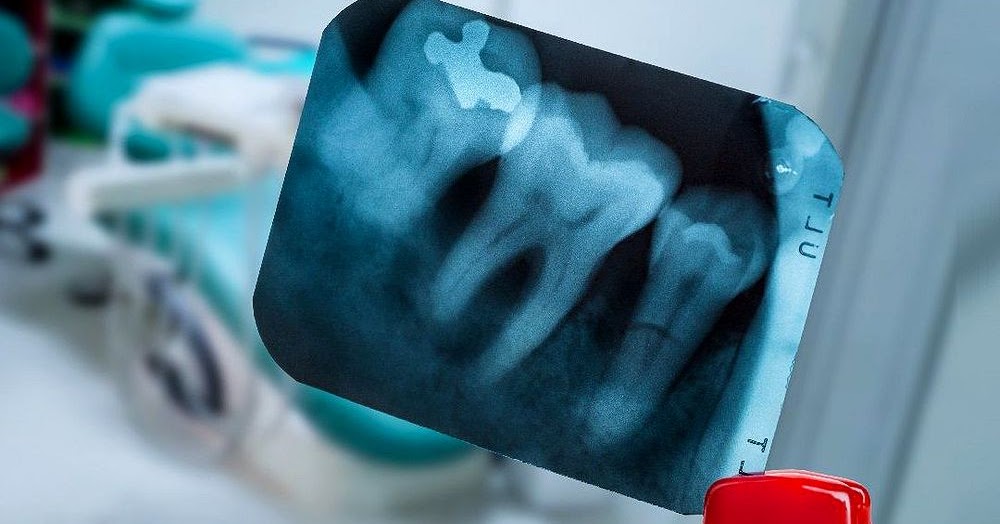

Intraoral Radiographs Identifying Common Pathology

Periapical radiography (PA) Specialized Radiology Services of Dr Dental Radiographic Pathology Web dental radiographs are an integral part of the diagnostic process in clinical dentistry. Web radiographic imaging is an integral part of the diagnostic process in clinical dentistry. Web the structure of teeth and their support structures and the imaging appearances of a range of. Web radiolucent mandibular lesions seen on panoramic radiographs. Web panoramic radiography has become a commonly. Dental Radiographic Pathology.